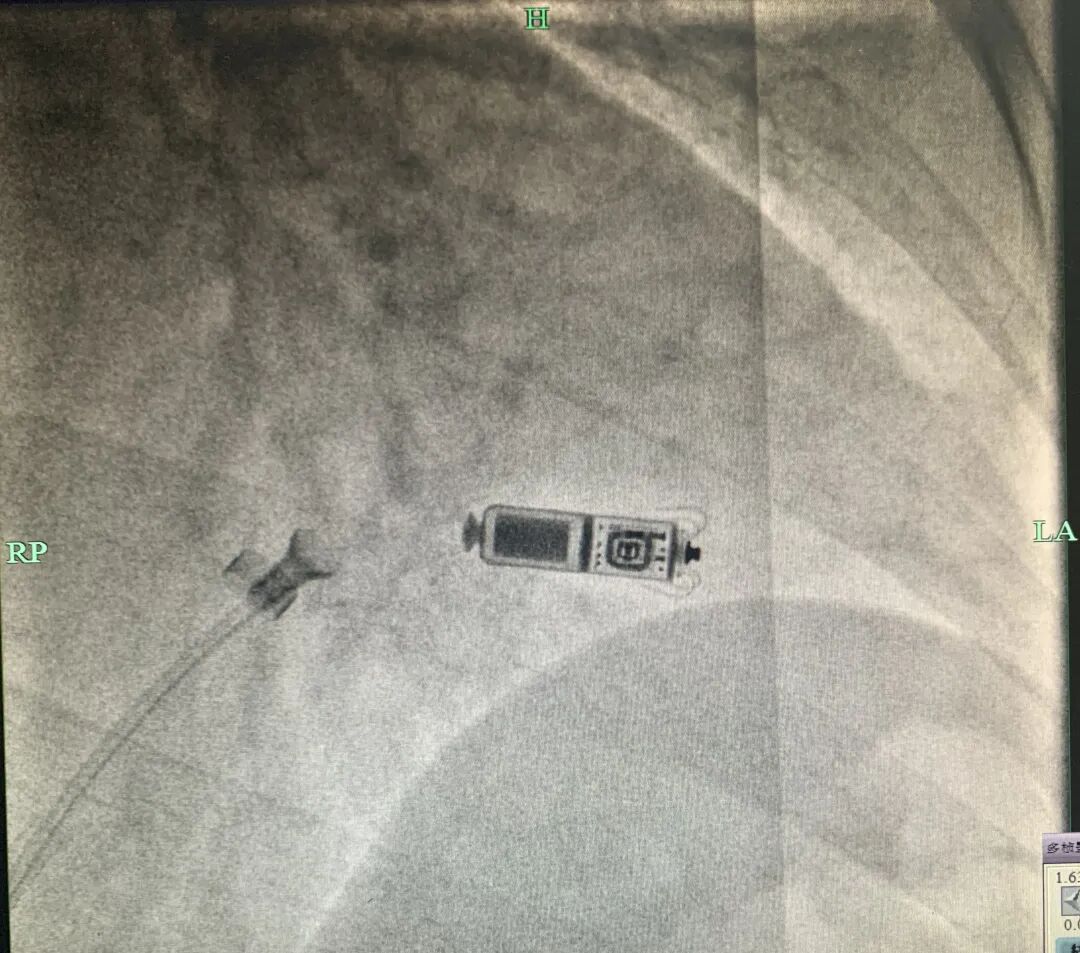

心脏起搏器、ICD

MRI检查:绝大多数不能做

在强磁场中,心脏起搏器、ICD可能会出现装置移位、起搏信号异常、除颤模式异常启动、电极升温等现象,严重时可导致装置损坏、心律失常甚至死亡等后果。

目前临床上应用的绝大多数心脏植入式电子设备都不能与MRI兼容。